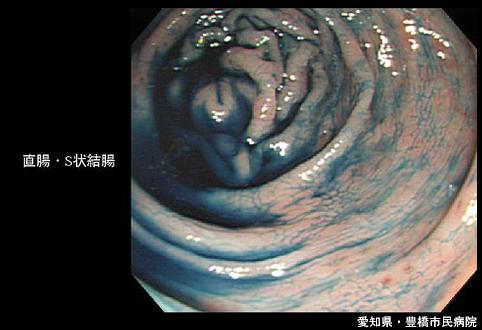

A case of inflammatory bowel disease with multiple esophageal lesions (strongly suspicious of Crohn's disease).

Inflammatory or ulcerative disease / lesions/Crohn disease

Location

Large intestine(Colon)/More than one of the above

Endoscopy